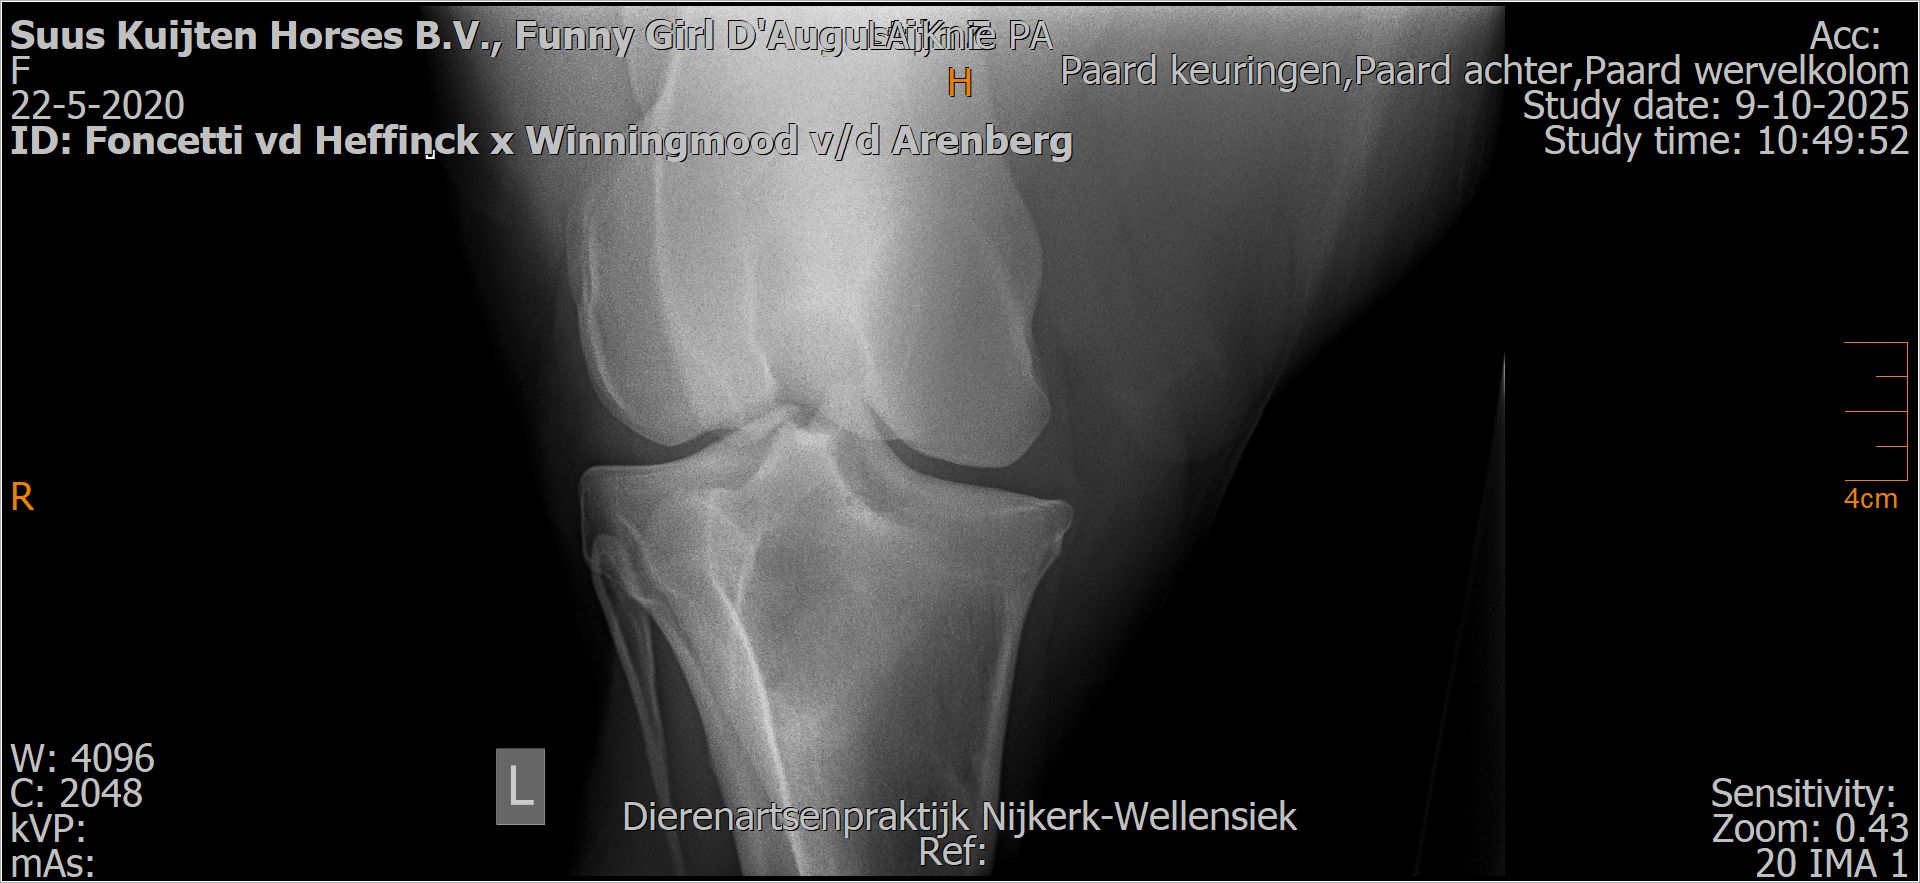

Funny Girl D'Augustijn Z

Röntgenfoto’s